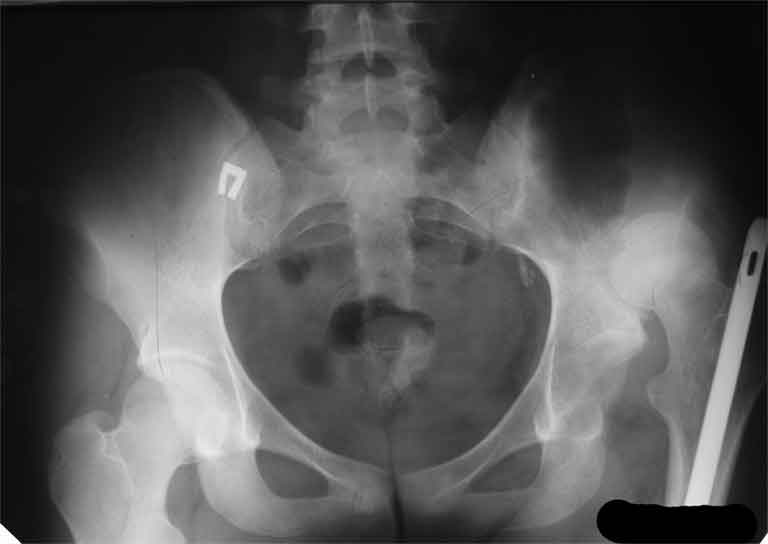

AV> опираясь на стул. На ногу не наступает. Укорочение 8 см. Иногда

А за счет чего такое укорочение? По снимку не видно соответствующего дефекта. Ну плюс приводящая контрактура - но все равно как-то уж больно много. Может, сделать снимки и таза обзорный с обоими проксимальными отделами бедра, и коенный суставов с приложенной линейкой какой?

The X ray that you provided does not show 8 cm of shortening. Perhaps you could send one showing the whole pelvis and proximal femurs.

I agree with Dr Eid's comments. The origin of the 8 cm leg length difference is a puzzle. Is this a clinical measurement? In that case contracture of the joint might affect the measurement. Can we see an AP pelvis to include both hip joints (including a calibration object with a known length) so that the difference in leg lengths that can be ascribed to the hip deformity and bony reabsorption can be measured. This sort of xray will help with templating for the TJR also. I would be very tempted to do a one stage procedure and accept some shortening. Shoe lifts should take care of a 3-4 cm difference.

До травмы проблем с ногой не было. Укорочения, болей и т.п. не отмечал. Сегодня перемерял укорочение - меньше 7 см намерять не

получается :)

По уровню малых вертелов (с учетом рентгеновского увеличения) получается 5 см. Клинически ногу низвести путем тракции невозможно. Из движений - сгибание до 40*, остальные движения "символические".